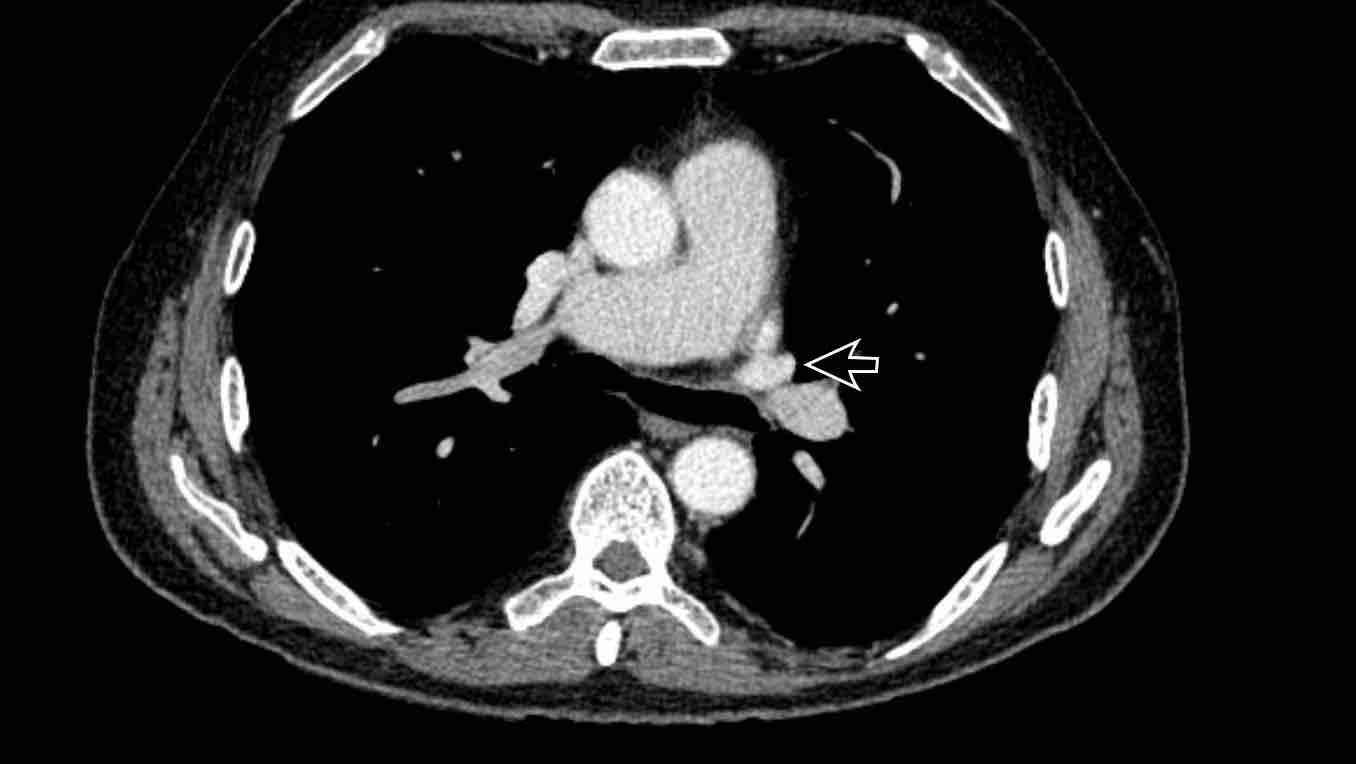

Hình ảnh

Bệnh nhân này được lên kế hoạch cắt thùy trên phải do ung thư phổi và bất thường mạch máu này ban đầu đã bị bỏ sót trên hình ảnh CT.

Những hệ quả trong phẫu thuật của bất thường như vậy nhấn mạnh tầm quan trọng của việc không bỏ sót các biến thể này.

Cuộn qua các hình ảnh.

PAPVR bên trái phát hiện tình cờ với dẫn lưu trên tim của máu từ thùy trên trái vào tĩnh mạch tay đầu trái (các mũi tên).